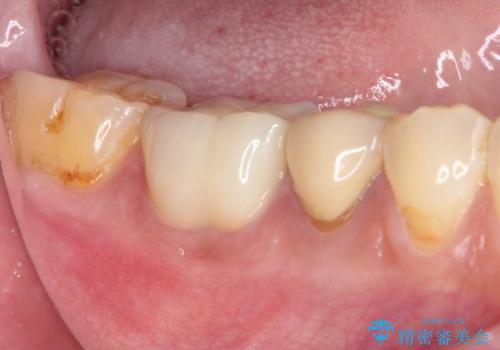

- 奥歯が欠けてしまった事を主訴として来院した患者様です。

頬側の欠けている範囲が大きく、以前治療した詰め物も大きいため、詰め物を外してむし歯を除去し、

形を整えて一度仮歯に置き換え、フルジルコニアクラウンにて補綴しました。

高強度のフルジルコニアクラウンは、強いかみ合わせでも壊れにくいです。

また審美的にも満足していただけました。